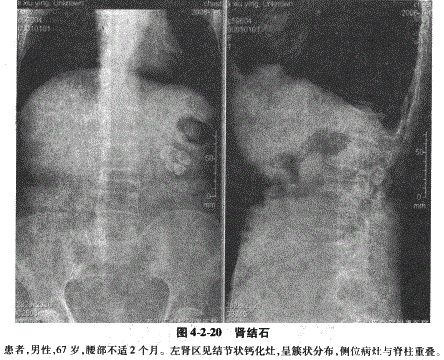

1.肾结石:在泌尿系结石中最常见,多为单侧发病,约10%为双侧发病。多见于尿路梗阻、积水、感染和黏膜损伤,临床上典型症状为疼痛、血尿。X线表现为肾窦区或其邻近部位高密度影,可单发或多发,单侧或双侧。结石密度可均匀一致、分层或浓淡相间,大小不一,形态可为类圆形、三角形、鹿角状、珊瑚状及桑葚状等,侧位与脊柱重叠(图4-2-20)。